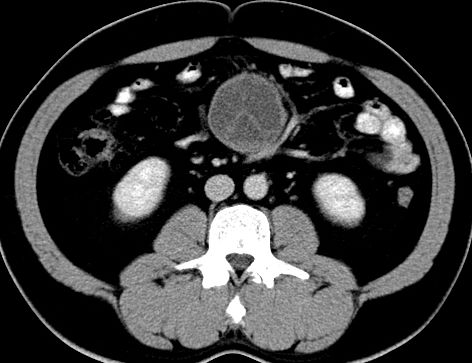

(腹腔)神经鞘瘤

男,48岁,间断性下腹不适1年。

手术探查

:距回盲部28厘米处肠系膜根部可见5*7cm左右包块,质中等硬度,活动度尚可,肝、胆、胰、脾肾未见明显异常。

病理

:(腹腔)

神经鞘瘤

,伴出血、坏死及囊性变,伴淋巴结反应性增生。

免疫组化结果

:sma(-), desmin(-), cd117(-), s-100(+++), nf(-),vimentin(+++).